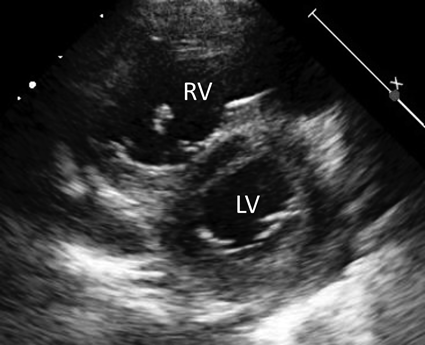

A Pediatric Case of Pulmonary Hypertension Associated with Congenital Bronchial Atresia